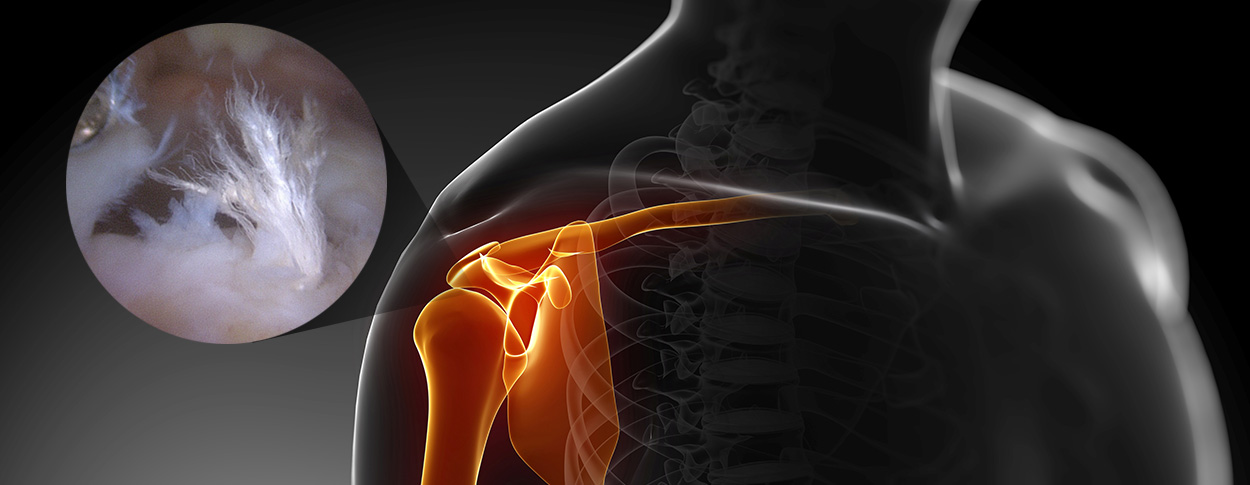

5mm 내외의 최소 절개 후 내시경을

삽입하여 치료 부위를 확인합니다.

의사가 치료 부위를 직접 확인하면서

손상된 조직을 봉합 혹은 제거 합니다.